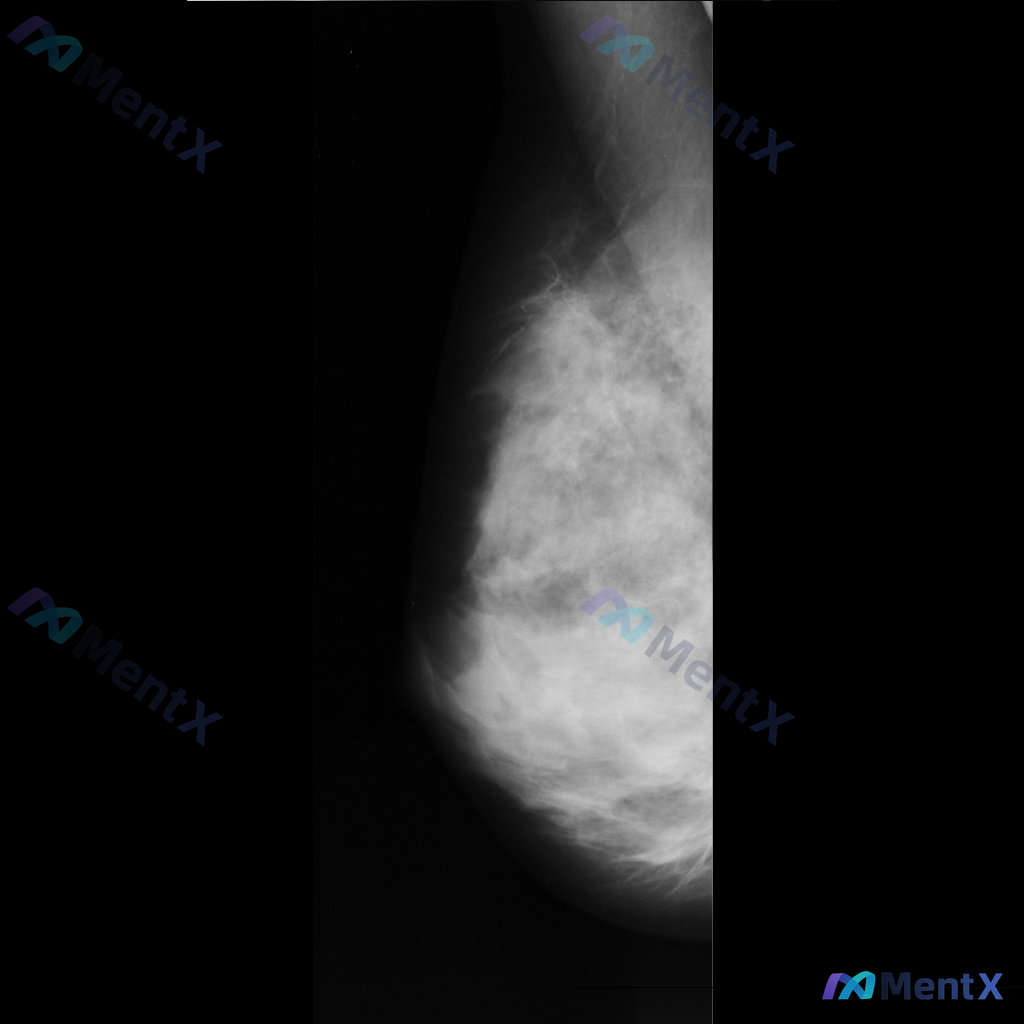

整理了一张乳腺钼靶影像的讨论资料,先和大家分享一下读片描述: 影像可见:不规则、高密度肿块/不对称致密影,伴有毛刺状边缘、结构扭曲和散在钙化。 目前考虑可能存在几种不同的异常方向,想先听听大家的第一反应——单看这组影像特征,你会先往哪种情况考虑? 也可以说说你最关注的是哪一点表现。

整理到一张乳腺钼靶影像的分析资料,先和大家同步一下核心表现: - 乳腺构成:不均匀致密型 - 主要异常:在乳腺中央偏上区域可见一个不规则形高密度肿块,边缘有毛刺样改变;围绕这个高密度影,周围的乳腺小叶和导管结构紊乱,向病灶中心牵拉。 目前暂时没有更多临床病史、查体或其他检查补充。想先问一下大家:单看...

整理到一组乳腺钼靶的影像资料,大家先一起看看: 影像表现: - 病灶位于乳腺上中部(大致外上象限)可见一局限性高密度肿块影 - 形态不规则,边缘有毛刺状改变 - 周围腺体结构有扭曲、牵拉征象 - 肿块内部或附近可见点状钙化,部分呈簇状分布 目前只有这组钼靶表现,大家先不补充更多临床信息的话,大家更倾...